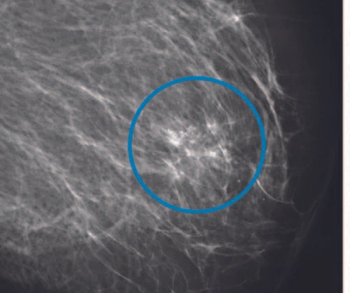

In a retrospective study involving mammography screening in over 114,000 women, researchers found that an artificial intelligence model had comparable specificity and sensitivity to radiologist screenings, reduced false positive results by 25 percent and reduced radiologist workload by more than 62 percent.